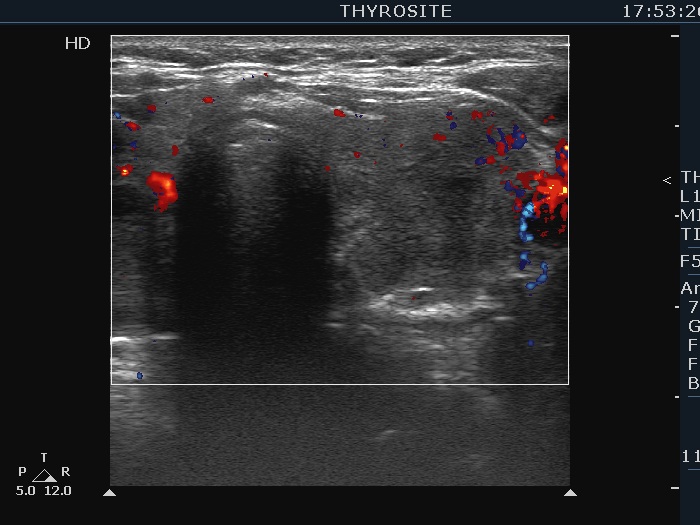

Graves' disease - case 2151 (ultrasonographic picture 6)

Left lobe, transverse scan, color Doppler mode. The vascularization is decreased.